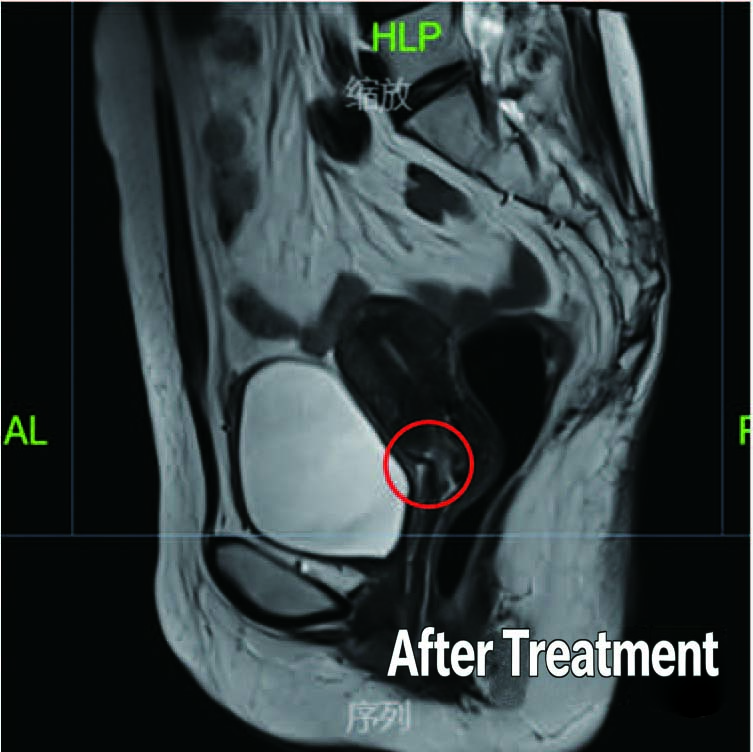

After Treatment

Patient: 53-year-old female

Diagnosis: Diagnosed Stage 111B Cervical Cancer in February 2020

Treatment History: Patient underwent chemotherapy at another hospital with unsatisfactory results.

Treatment at Our Hospital: Definitive radiotherapy for cervical cancer (External beam radiotherapy+ brachytherapy)

Outcome: Significant reduction in the size of the tumor observed post-treatment, with complete disappearance of the large tumor.